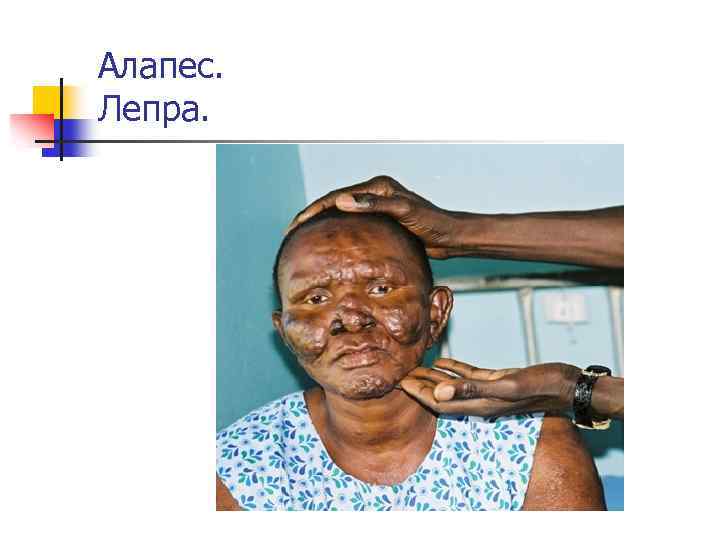

Алапестік гранулеманың ерекшеліктері n n негізі макрофагтар, плазмалы жасушалар, олардың арасындағы цитоплазмасында май вакуольдары, қораптағы сигаралар сияқты ретпен жайғасқан қоздырушылар бар макрофагтар лепромалық жасушалар (Вирхов жасушалары) алапестік түйнек, яғни лепромалар түзеді. Лепромалық жасушалар бұзылған кезде босаған микобактериялар лепромадағы жасушалардың арасына шоғырланады.

Алапес. «Арыстан пішін» Лепра. «Львиная морда»

Алапес. Лепра.